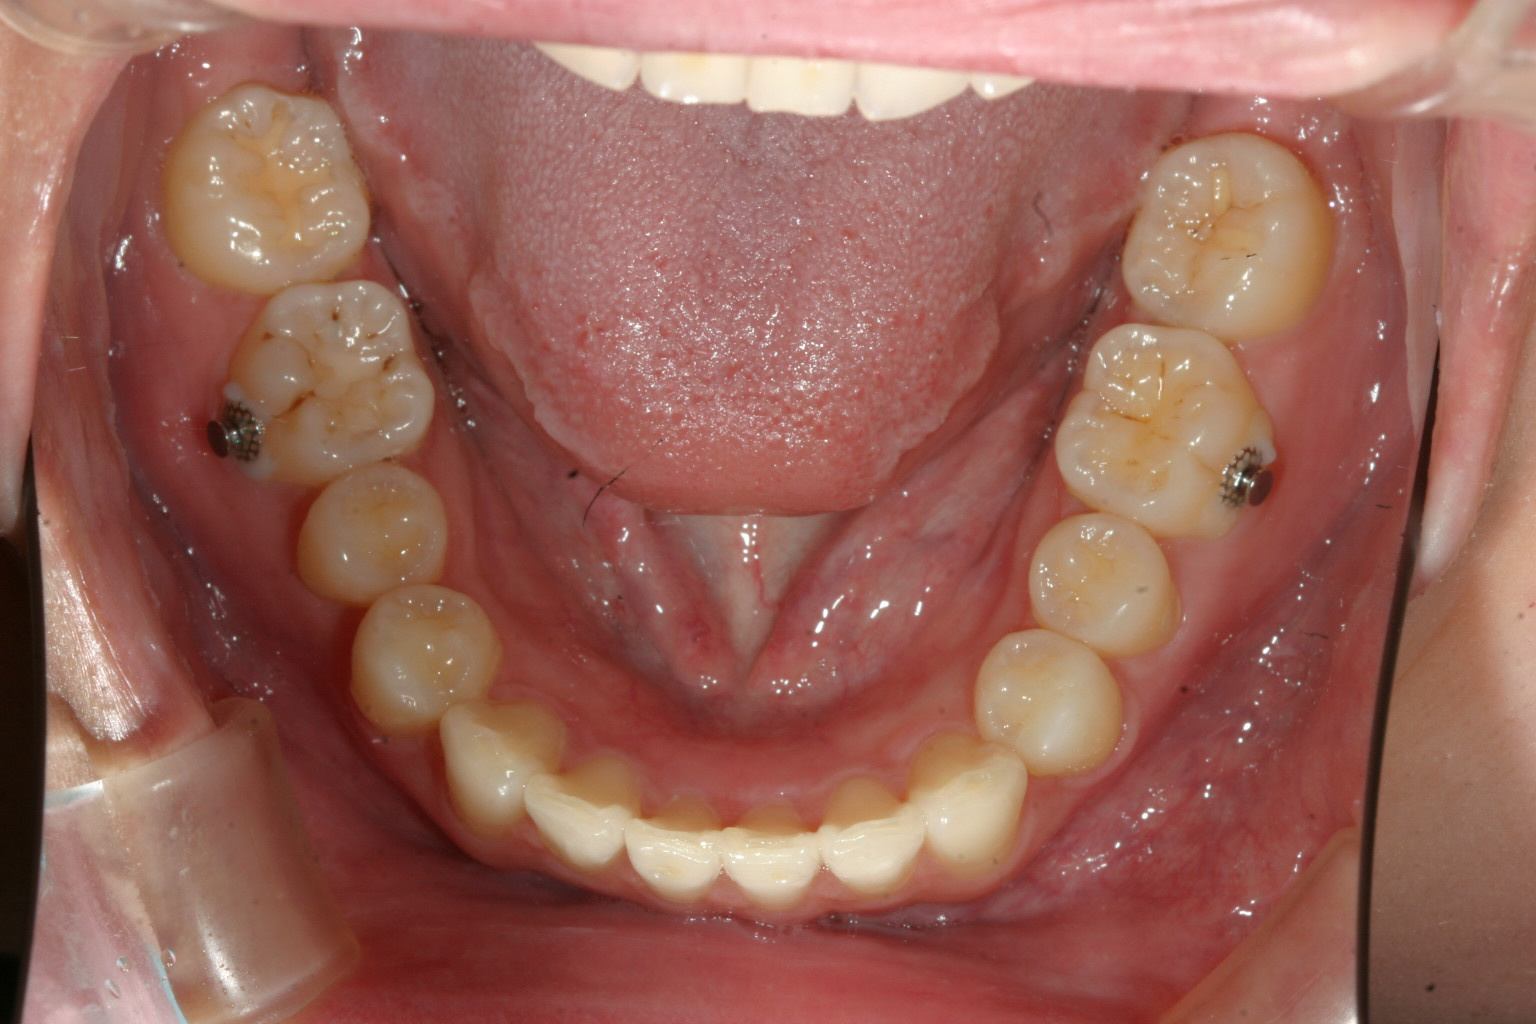

前歯部に自家製のジグ咬ませて左側にアップダウンエラスティックを使用してます。

前歯部に自家製のジグ咬ませて右側にアップダウンエラスティックを使用してます。

僅か1年2ヵ月で抜歯もせずここまで治りました。 如何でしょうか?